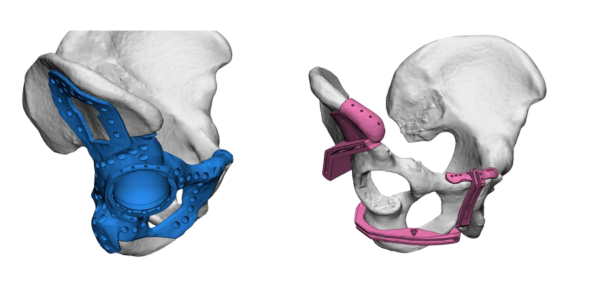

Dr. Himanshu Rohela leading Onco Orthopedic surgeon in Mumbai, Maharashtra after studying the scan and his previous treatment records, concluded that the patient is suffering from cancer of right pelvic bone having tumor. The challenge was to save the leg thus using Patient Specific Cutting Guides and Patient Specific Hip implant. Incredible team discussed with Dr. Rohela, the designing and entire manufacturing process. It initially started with surgical planning and case simulation with the help of US FDA & CE approved Materialise Mimics software by superimposing CT & MRI DICOM data & Anatomical Model. As Anatomical model maintained 1:1 ratio with the anatomy, hence showed excellent detailing of the defect, the model was also used to design jigs & implant on actual bone, which further helped the pre surgical planning. Once the planning was finalized, the surgery was accompanied with not only Customized Implant but also Cutting guides & Jigs. Read more

Implant was manufactured under ISO 13485 guidelines & tested to give an accurate fit & utmost safety.

Cutting Guides and Jigs from 3D Incredible helped the Surgeon to give an accurate cut and complete the surgery in one go. Once the resection was done, customized implant from 3D Incredible was implanted. Implant was manufactured using Ti6Al4V- ELI, a biocompatible material; as per anatomical requirement, contour and bone thickness which are patient specific. Read more